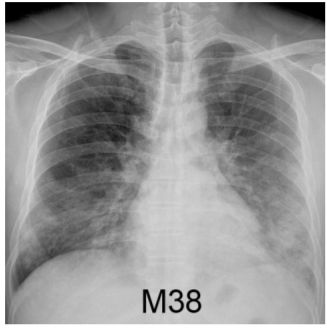

6. 男性38歲,有吸煙史,因發燒、咳、喘來急診,胸部X光如圖1,隔天喘加劇、胸部X光如圖2,其最可能診斷為何? (A) 流感肺炎 (B) 葡萄球菌肺炎 (C) 綠膿桿菌肺炎 (D) 克雷白 ( Klebsiella ) 菌肺炎 (E) 退伍軍人症肺炎